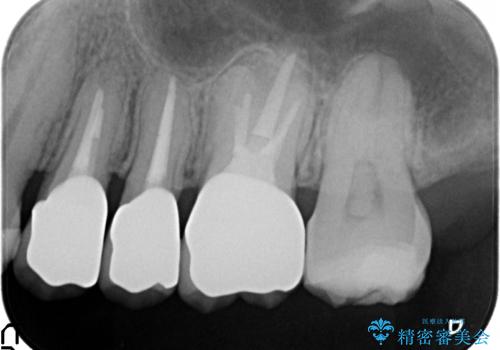

銀歯を除去したところ歯茎よりも深い位置まで虫歯があったため、歯冠長延長術(歯周外科)を行いました。

その後歯茎の回復を待つ間に再根管治療を行い、歯茎の回復後オールセラミッククラウンにて補綴を行いました。

今回用いたオールセラミッククラウンはジルコニアフレームという白い素材の上にセラミックを盛っているため、審美性が非常に高いのが特徴です。

また、ジルコニアは人工ダイヤモンドの材料にも使われているほど高い強度を持っており、そのためオールセラミッククラウンは審美性だけでなく、奥歯やブリッジの補綴も可能とするクラウンです。